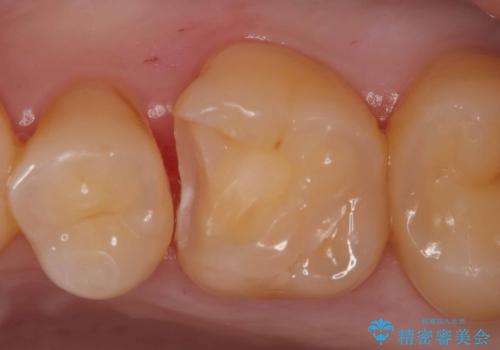

- 定期検診で虫歯が見つかった患者様です。ハイブリッドインレーで治療を行いました。

定期検診で虫歯が見つかった患者様です。

ハイブリッドインレーで治療を行いました。

ハイブリッドインレーはセラミックインレーとは違い、セラミックとプラスチックの混合物です。保険治療の材料よりは優れていますが、プラスチックが混ざっている分、セラミックインレーには劣ります。型取りの材料はセラミックインレーの時と同様のシリコン印象材を使用しています。